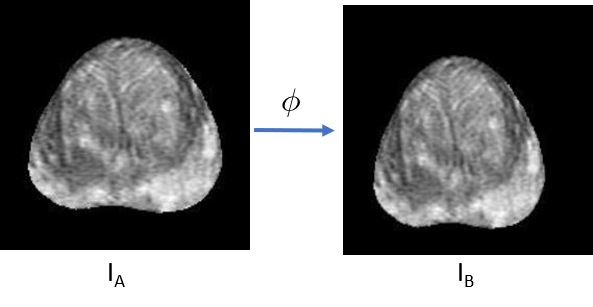

Since the ground truth spatial correspondences between the MRI and histopathology images are lacking, we trained our neural networks using uni-modal image pairs generated by synthetic transformations (Figure 4).

Figure 4: Generating training dataset by applying known transformations. IAsubscript𝐼𝐴I_{A} is the original image, ϕitalic-ϕ\phi is either an affine or thin-plate spline transform, and IBsubscript𝐼𝐵I_{B} is the deformed image by applying ϕitalic-ϕ\phi to IAsubscript𝐼𝐴I_{A}. Each tuple (IA,IB,ϕ)subscript𝐼𝐴subscript𝐼𝐵italic-ϕ(I_{A},I_{B},\phi) is considered as one training example.

For each 2D image IAsubscript𝐼𝐴I_{A}, we applied a simulated transformation ϕitalic-ϕ\phi to deform it into the image IBsubscript𝐼𝐵I_{B}. The 3-tuple (IA,IB,ϕ)subscript𝐼𝐴subscript𝐼𝐵italic-ϕ(I_{A},I_{B},\phi) will be used as one training example. The transformation ϕitalic-ϕ\phi can be either an affine transform or a thin-plate spline transform. To guarantee the plausibility of the simulated transformations, the variables used to parameterize the transformations were randomly sampled from bounded intervals. When simulating the affine transformations, the rotation angle ranged from -10 degrees to +10 degrees, the scaling coefficients ranged from 0.8 to 1.2, the shifting coefficients were within 5% of the image size, and the shearing coefficients were within 5%. When simulating the thin-plate-spline transformations, the movement of each control point was within 5% of the image size. We chose these intervals as they represent typical transformation ranges we observed when using RAPSODI and were shown to be sufficiently wide to cover the transformations observed in our diverse patient cohorts. For the training, we used 1,390 MRI and histopathology images and the corresponding prostate masks of 99 patients from Cohort 1. Prostate masks were used to train the affine registration network and masked MRI and histopathology images were used to train the deformable registration network. Although our registration neural network was trained with image pairs of the same modality, we will show that it can be generalized to the multi-modal registration of MRI and histopathology images for all three cohorts.